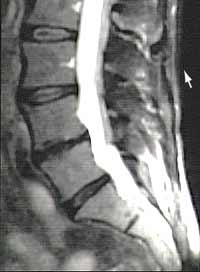

MRI

Prolaps auf der Höhe L4-L5

Beim MRI, auch Kernspintomographie genannt, werden im Gegensatz zum CT keine Röntgenstrahlen verwendet. Es kann die Wirbelsäule mit eventuellen Vorwölbungen der Bandscheiben in den Spinalkanal im Querschnitt und zusätzlich auch im Längsschnitt darstellen. Es ist vor allem in der Darstellung des Nervensystems und der Weichteile, also gerade der Bandscheiben und der Nervenwurzeln, dem CT überlegen.